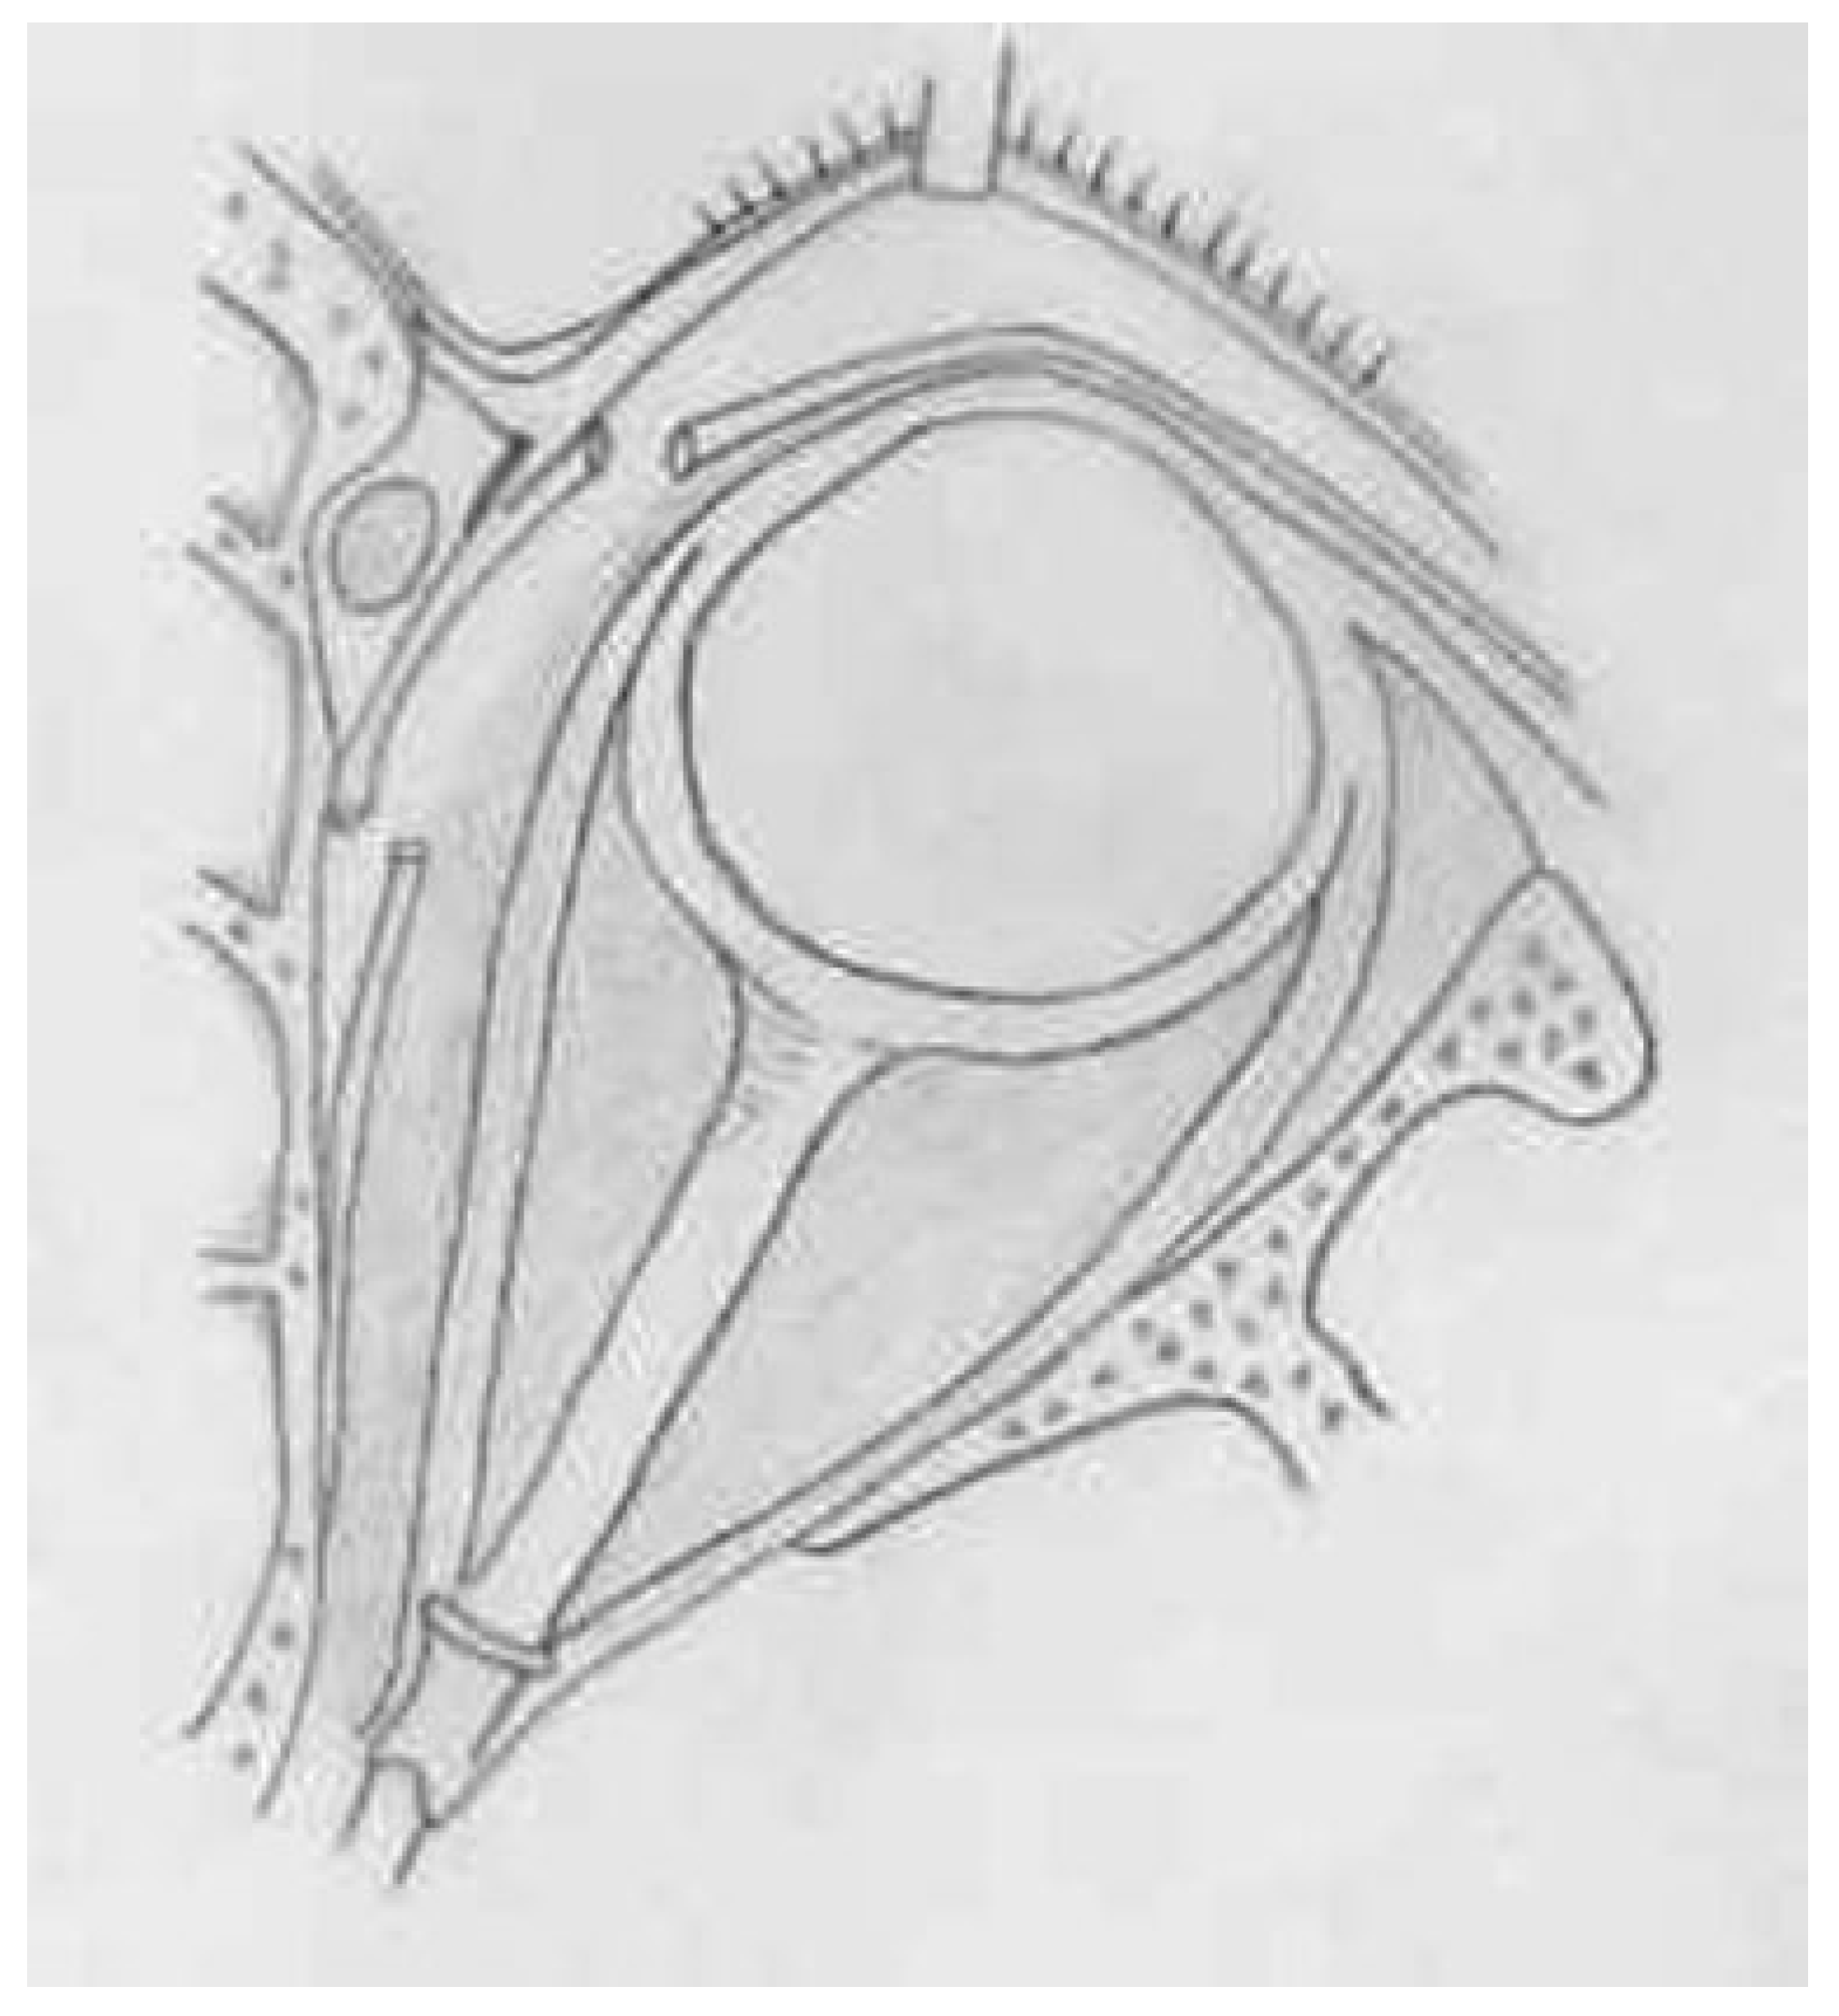

:SURGICAL TECHNIQUE